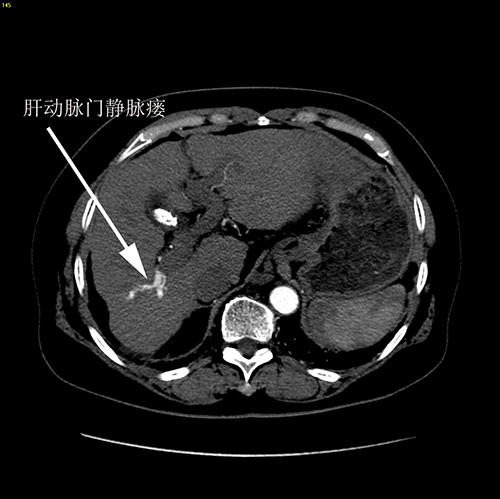

门脉高压、右肝动脉门静脉瘘、胆囊结石----脾切除、贲门周围血管离断、肝右动脉结扎、胆囊切除